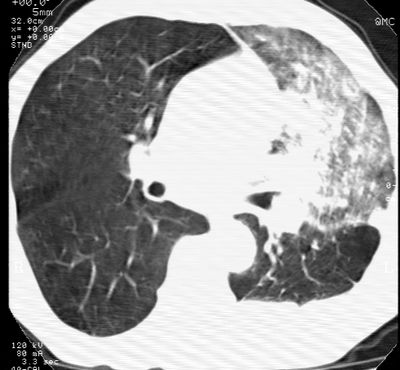

标题: CT24000:M65,胸痛,胸闷月余,既往慢支,肺气肿,肺心病 [打印本页]

标题: CT24000:M65,胸痛,胸闷月余,既往慢支,肺气肿,肺心病

左肺门肿块,相应支气管闭塞,左肺上叶、舌叶大片及散在高密度影,部分呈不张改变,两肺纹粗乱,左侧胸腔积液。考虑左侧中央型肺癌伴阻塞性改变。

左肺门见巨大软组织肿块影,直径约--,境界清,左上肺叶支气管变窄,左上肺舌叶见大片状密实影,余肺纹理增多、紊乱、纤细、部分网格状,两肺透亮度增高,纵隔内见增大多发淋巴结影,心影略左偏,左侧少量胸腔积液。

左侧中央型肺癌伴左上肺舌叶不张、纵隔淋巴结转移,左侧少量胸腔积液。